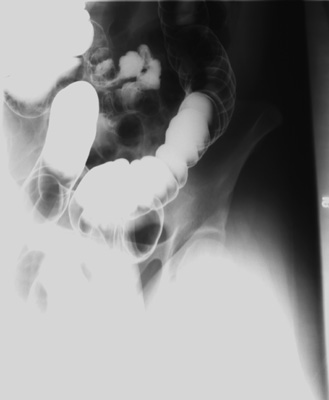

- 15 degree RAO view of rectosigmoid with 35 degree caudad central ray - 14" x 17"

cassette